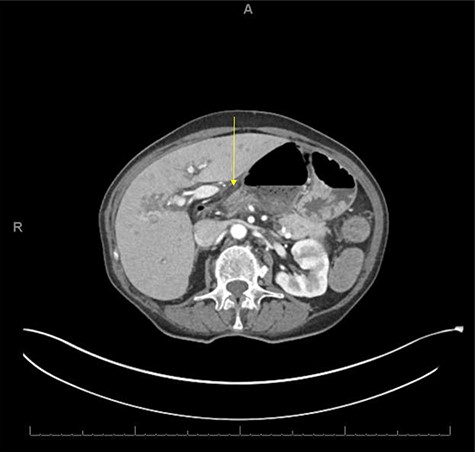

An 80-year-old female with past medical history of Crohn’s disease (diagnosed in 1998 and managed with Adalimumab) and no prior abdominal surgical history who presented with 1-day history of severe epigastric pain associated with nausea and emesis. Her last colonoscopy was 3 years ago (unremarkable), and last Crohn’s flare was a 1 year beforehand. On examination, patient’s abdomen was soft with severe epigastric tenderness and an appreciable bulge. Labs showed normal lactate (1.1) but mild leukocytosis of 12.5 and no other gross lab abnormalities. Patient underwent computed tomography (CT) scan of abdomen and pelvis which showed a transverse colon herniating through the FOW and causing a closed-loop obstruction (Figs. 1–3). Patient was immediately decompressed with a nasogastric tube and was emergently taken to the operating room for a diagnostic laparoscopy. Intraoperatively, the transverse colon was noted to have herniated through the FOW into the lesser sac. The incarcerated transverse colon appeared immensely dilated and hyperemic. With careful traction and gentle counter pressure, the transverse colon was completely reduced from the FOW back into the abdominal cavity. On inspection after reduction, the small and large bowel appeared grossly viable and well-vascularized along with adequate peristalsis. The FOW was closed with 2-0 ethibond running suture by suturing the peritoneum adjacent to the portal triad down to the retroperitoneum just lateral to the inferior vena cava. The patient tolerated the procedure very well and brought to the recovery room in stable condition. Postoperatively, the patient did very well. On postoperative Day 1, the patient was discharged home. Subsequently, the patient was seen in the office on postoperative follow-up Day 7 and was found to be doing well with no complaints.

CT axial view showing proximal and distal loops of transverse colon are seen traversing through the foramen of Winslow.